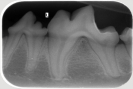

Zahnröntgen

(9 pictures)

Galerie Zahnröntgen